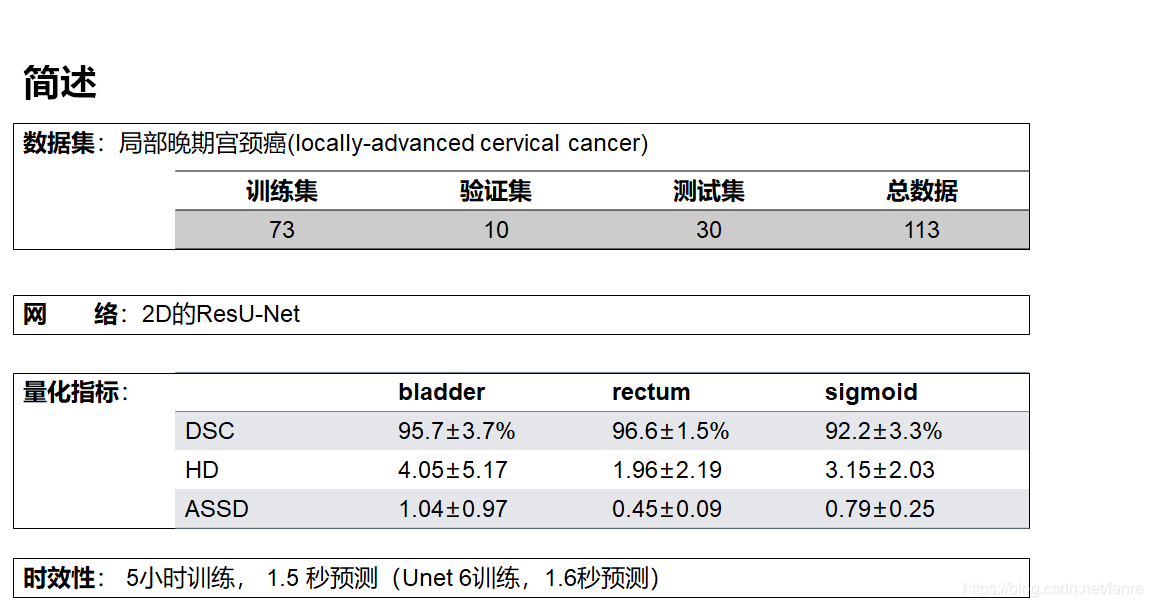

基于深度学习的宫颈癌高剂量率后装放疗危及器官自动勾画

基于深度学习的宫颈癌高剂量率后装放疗危及器官自动勾画